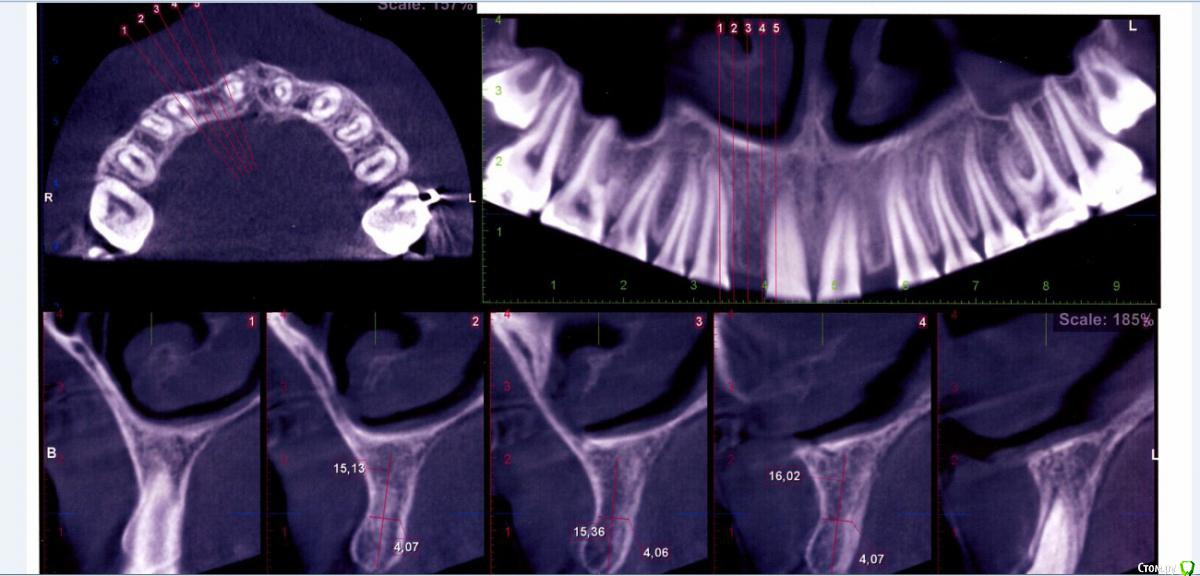

КТ лето 2015г.:post-461-0-66686400-1456407220_thumb.jpgpost-461-0-08014000-1456407222_thumb.jpg